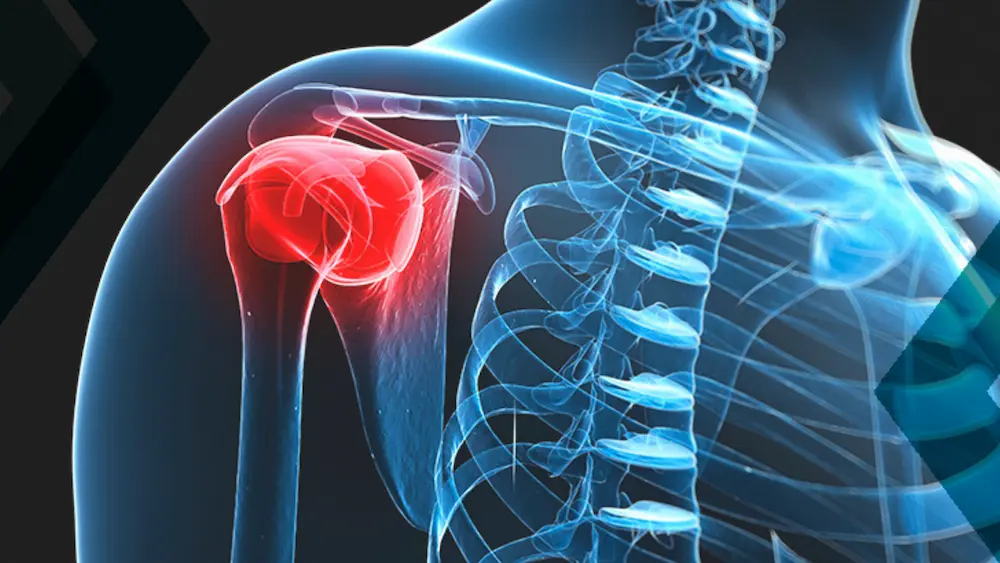

Capsulite Adesiva

O que é a Capsulite Adesiva?

A capsulite adesiva, também conhecida como “ombro congelado”, é uma condição que causa dor e rigidez no ombro, resultando em limitação significativa dos movimentos. Esta condição pode se desenvolver gradualmente e muitas vezes afeta pessoas entre 40 e 60 anos de idade, sendo mais comum em mulheres. Entender essa condição e como tratá-la é fundamental para restaurar a mobilidade e melhorar a qualidade de vida.